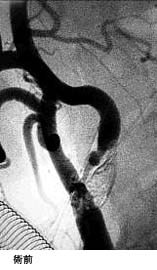

頸動脈狭窄症に対するステント留置術

(現在、ステントは保険適応となっておりません。)